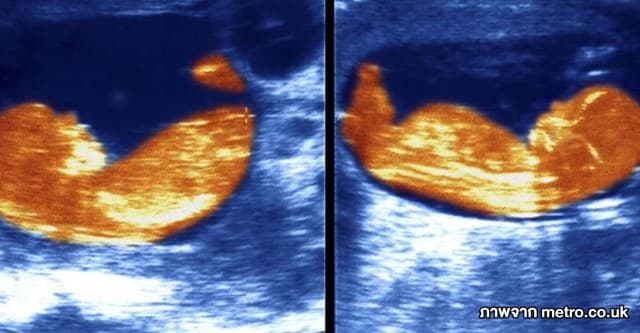

เวียดนามพบฝาแฝดเกิดจากแม่คนเดียวกัน . . . แต่คนละพ่อ